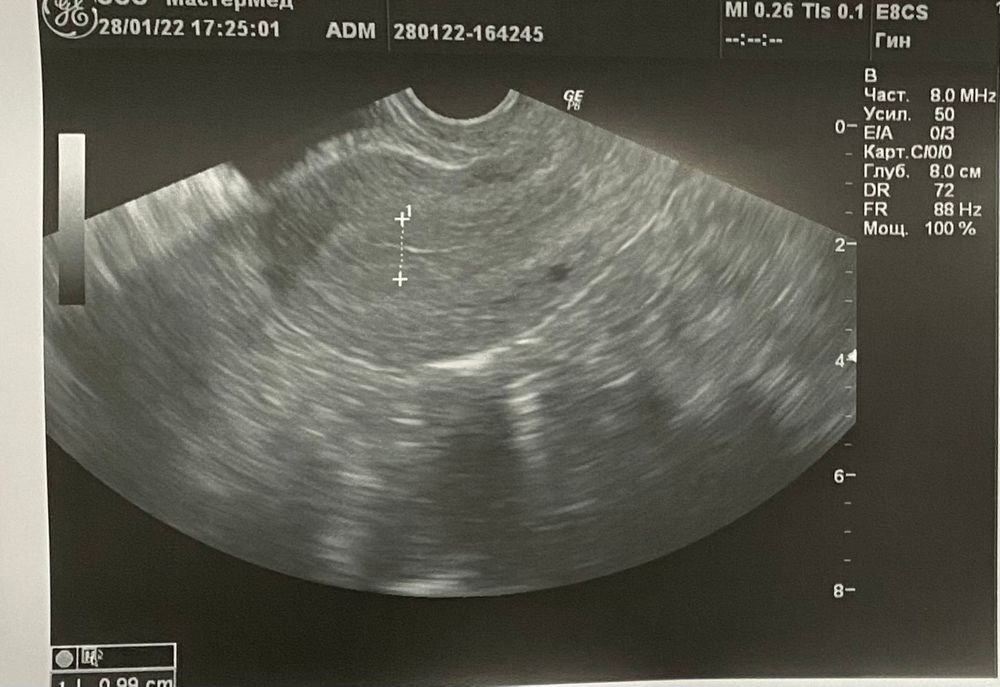

Вместо М пришли кровомажущие выделения (17.01-20.01),появились боли в спине, внизу живота при ходьбе, сонливость и усталость,а так же боль при ПА.Вчера делали узи на приём в среду.